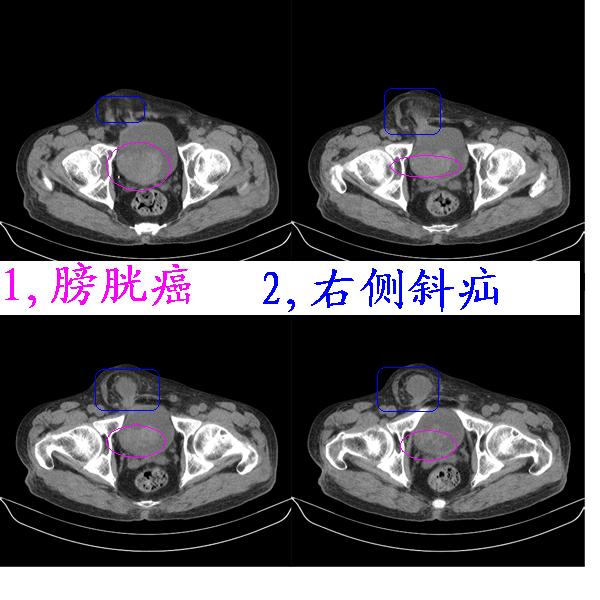

考虑膀胱ca,右侧腹股沟斜疝。

1、膀胱内占位性病变,膀胱癌可能性大。

2、腹部沟斜疝。

膀胱三角区右侧可见较大软组织肿块,分叶状,内可见更低密度区,ct做完后本人检查病人发现病人耻骨联合上稍偏右见一突出的包块影,质地柔软,平卧位手压后可以回缩.站立位突出明显!考虑腹股沟斜疝,疝内容物为膀胱.膀胱内肿物考虑1炎性赘生物2平滑肌肉瘤(有多年血尿史,本次加重且抗炎不好转)3膀胱癌

1.膀胱内软组织肿快,有点状钙化,前列腺不大.膀胱癌.

2.右侧腹股沟斜疝。

3.双肾平扫未见异常.

1、右侧腹股沟斜疝,疝内容物为膀胱;2、膀胱右后壁肿块,考虑膀胱癌